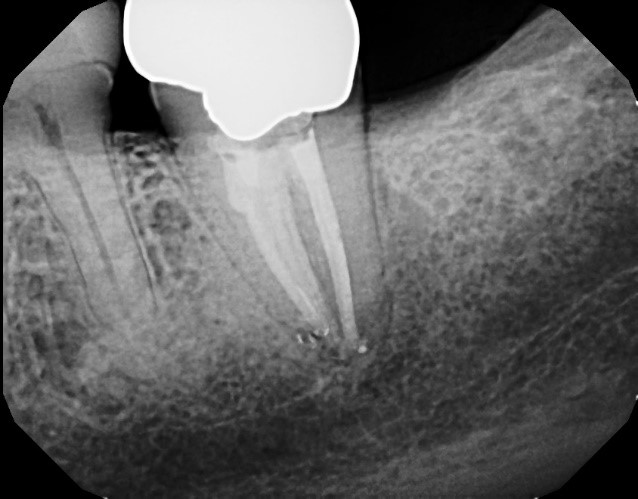

Here is a case in point: A long-term patient with an endodontically treated molar managed with a clinically acceptable crown presents with a new periapical asymptomatic lesion (Fig. 3). The diagnosis, based on radiographic and clinical history, is a recurrent periapical abscess due to microleakage. The tooth is adequately re-treated by a skilled endodontist and restored.

Less than 12 months later, the tooth develops a localized distal 9 mm periodontal pocket with bleeding on probing (Fig. 4). Upon extraction of the tooth, the diagnosis of a vertical distal root fracture is confirmed by direct observation under magnification. Therefore, it’s important to consider the possibility of occult root fractures being present whenever restorative dentistry is planned.

suggests a vertical fracture, combined with a localized 9 mm periodontal pocket.